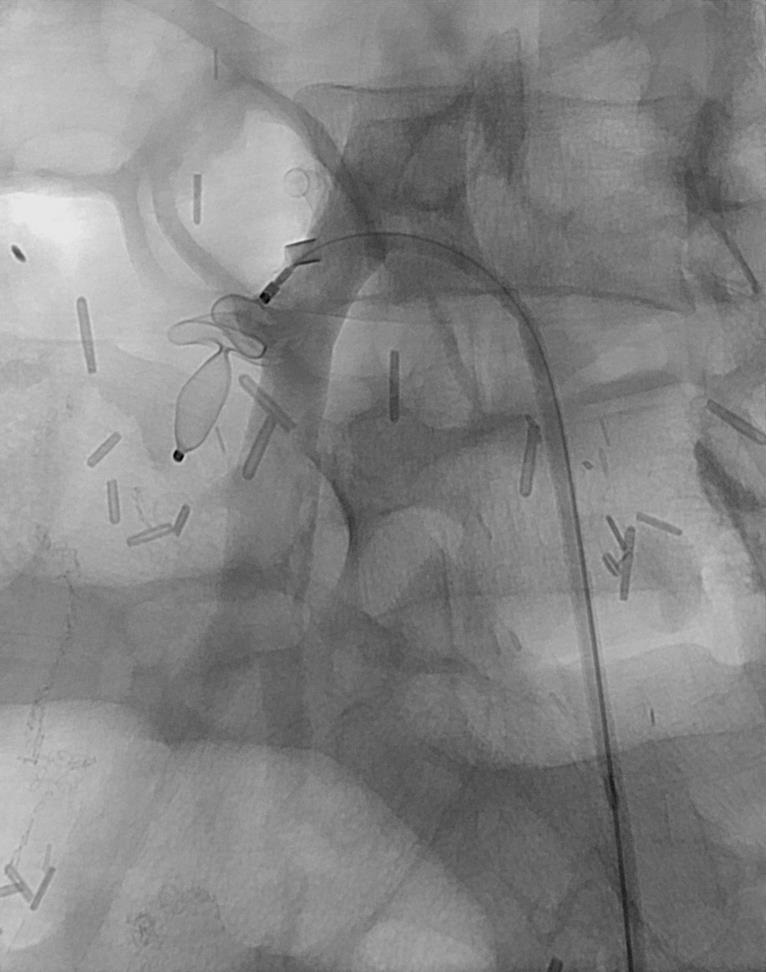

静脉畸形

静脉畸形引流静脉栓塞

| 经头皮针穿刺静脉团显示为慢血流静脉畸形和它的引流静脉 | 经静脉团穿刺引入5F导管至引流静脉并释放AVP IV 血管塞 |

|

| 引流静脉闭塞 | 引流静脉闭塞后进行畸形血管团的栓塞治疗 |